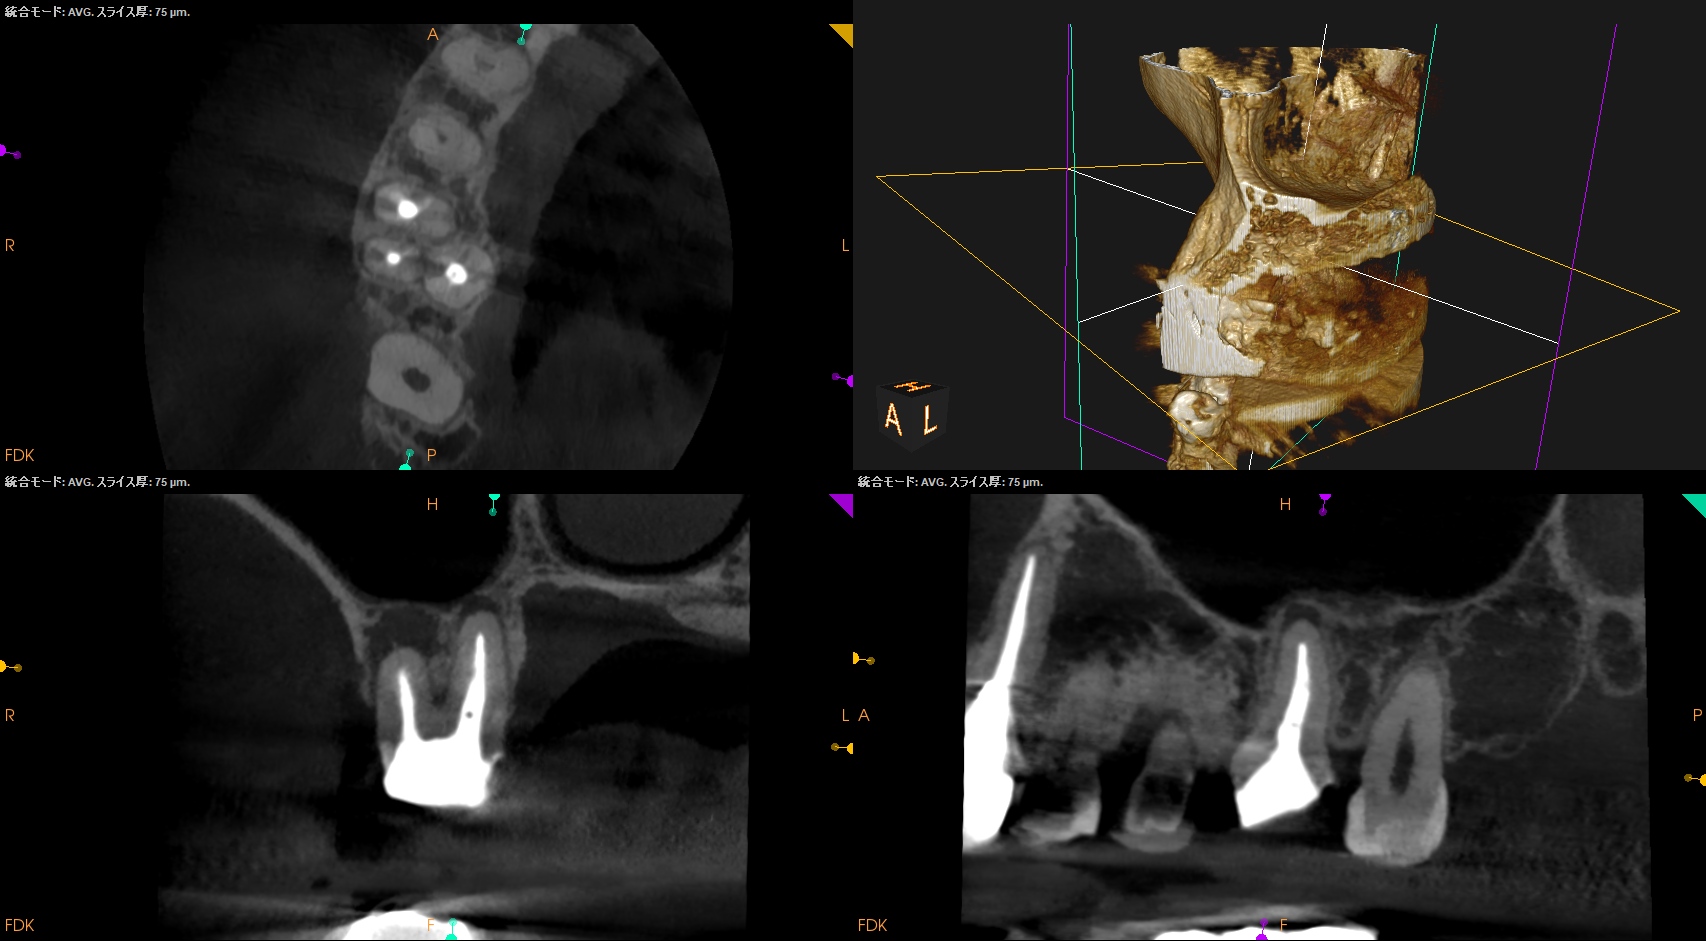

CBCT(2024.7.1)

#3

MB

DB

P

MB,DB,Pと3根全てに病変がある。

しかも形成が不完全だ。

再根管治療が濃厚である。

#14

MB,DBには病変がないが、Pに存在する。

これは頭が痛い。

パラタルフラップも困難なケースだからだ。

#16